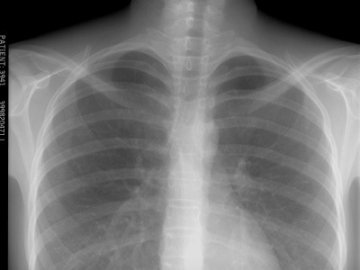

Захворюваність на туберкульоз у пострадянських країнах – увосьмеро вища, ніж у Європі

Туберкульоз не оминув жодної з країн Європи, але найбільшою мірою він поширений у всіх 15 пострадянських країнах, а також у Болгарії, Румунії і Туреччині.

Як зазначив Огтай Гезалов з Європейського бюро ВООЗ, в цих 18 країнах рівень туберкульозу залишається майже у вісім разів вищим, ніж у Західній Європі, тобто становить приблизно 69-70 випадків на кожні сто тисяч населення.

В інших країнах європейського регіону ВООЗ цей показник складає близько восьми випадків на кожні сто тисяч населення.

У цілому в 2010 році в країнах регіону було зареєстровано 309 648 нових випадків туберкульозу. Це на 2,6% менше в порівнянні з 2009 роком.

Ці цифри підтверджують, що за минулі п'ять років у масштабах регіону спостерігалося загальне зниження числа зареєстрованих випадків. Проте серйозною проблемою для досягнення мети ліквідації небезпечної хвороби є спостережуване зростання числа випадків туберкульозу з множинною і широкою лікарською стійкістю.

«У нашому регіоні спостерігаються найнижчі показники успішності лікування ТБ і найвищі рівні туберкульозу з множинною і широкою лікарською стійкістю в світі, — сказала директор Європейського регіонального бюро ВООЗ Жужа Якаб.